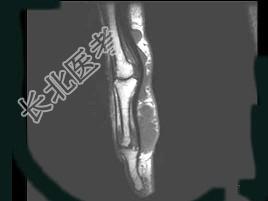

- 单项选择题女,77岁, 发现右手部肿块2周,结合图像, 最可能的诊断是 ( )

A、肌内脓肿

B、多发性腱鞘囊肿

C、骨囊肿

D、血管瘤

E、以上都不是